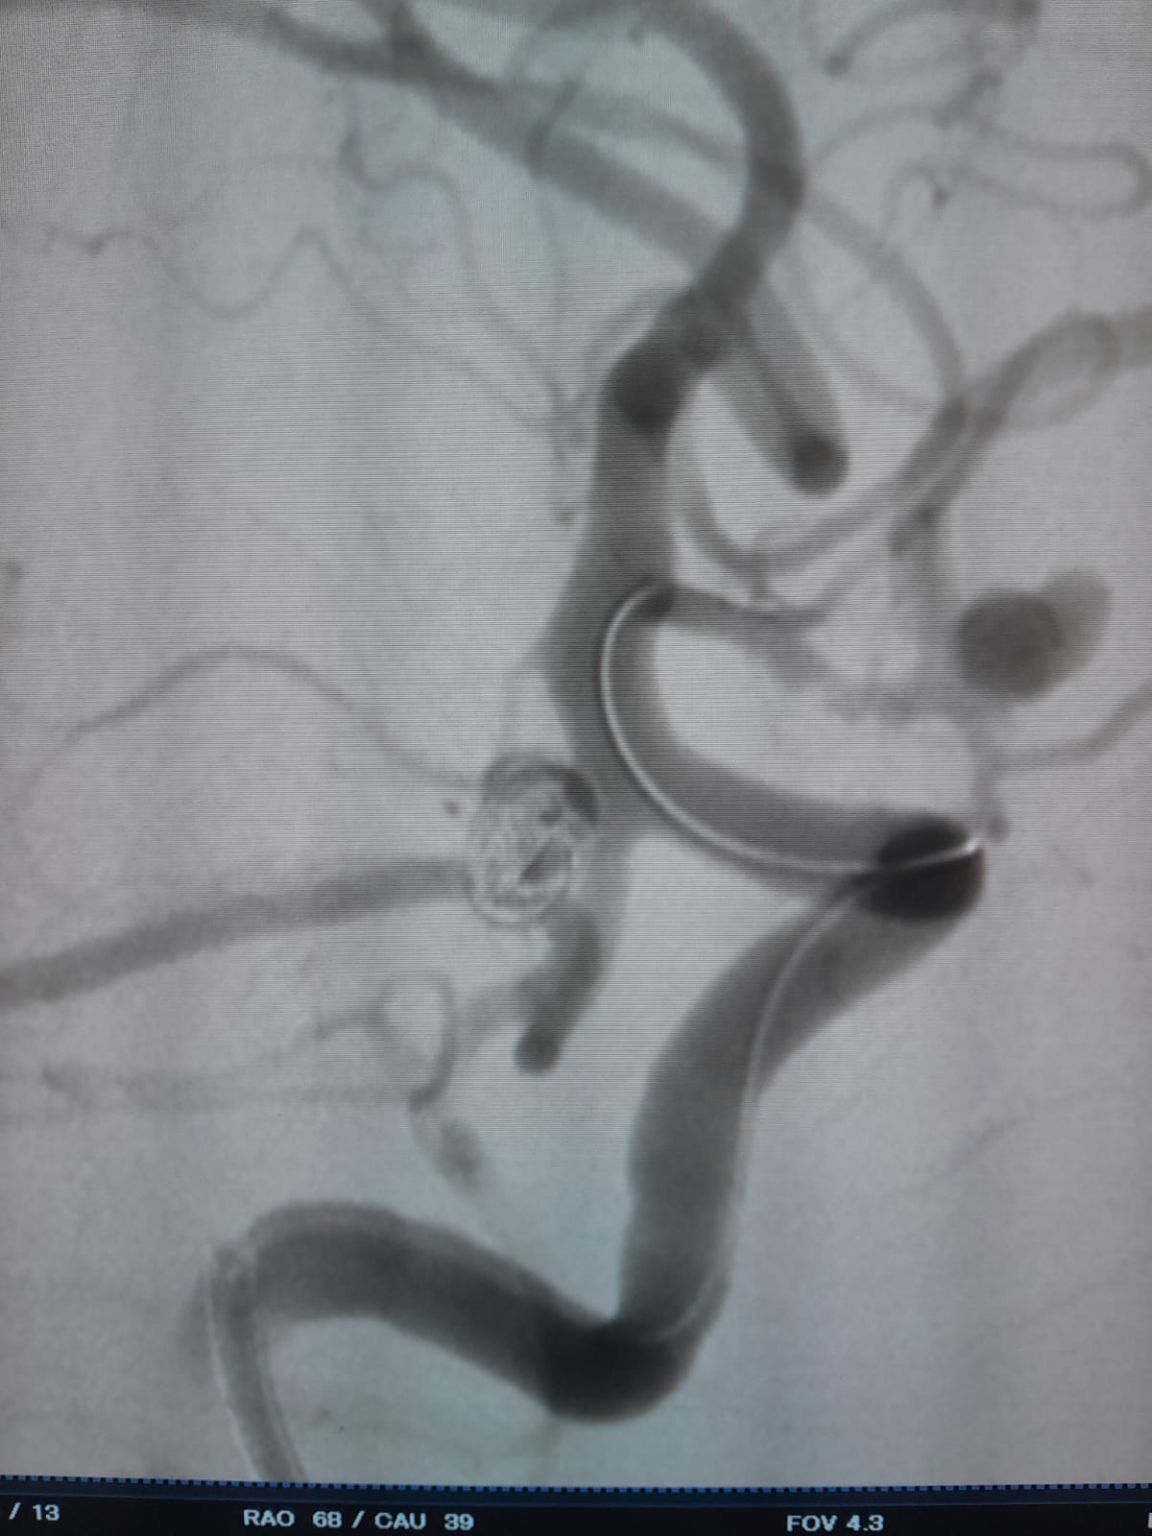

後部通信動脈動脈瘤 (再治療)

フォローアップ中に、以前に治療された後部通信動脈動脈瘤に残留物が見られました。 チームはFrepassを使用してサイトに再アクセスしました®使い捨てマイクロカテーテル (TJMC18 Plus) および首尾よくNuvaを展開しました®理想的な壁の配置と優れた流れの迂回を実証したフローダイバーター (TJED-D-4.5-16) は、非常に満足のいく治療結果につながります。